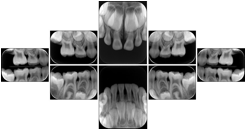

1. A patient in rural Canada visits a general ophthalmologist and is found to have diabetic macular edema. The general ophthalmologist would like to discuss the case with a retina specialist before performing laser surgery. A fluorescein angiogram is done with multiple retinal images taken in a timed series after an intravenous injection. The images along with a Structured Display are shared via a Health Information Exchange with a retina specialist in Calgary, who opens them using his Ophthalmology EMR software and consults via phone with the general ophthalmologist. Both physicians view the images in the same layout so the retina specialist can provide accurate guidance for treating the patient.

2. A patient in rural Iowa visits his primary care physician for management of diabetes. Three non-mydriatic (patient's eyes are not dilated) photographs are taken of the back of each eye, and forwarded electronically along with a Structured Display to an ophthalmologist in Iowa City. The ophthalmologist reads the photos in an agreed upon layout so there is no mistake about what portion of which eye is being viewed. The ophthalmologist is able to tell the primary care physician that his patient does not need to come to Iowa City for face to face ophthalmologic care, but that there is a particular view of the left eye that should be photographed again in 6 months.

Ophthalmic Retinal Study Structured Display

Figure OO-3. Ophthalmic Retinal Study Structured Display